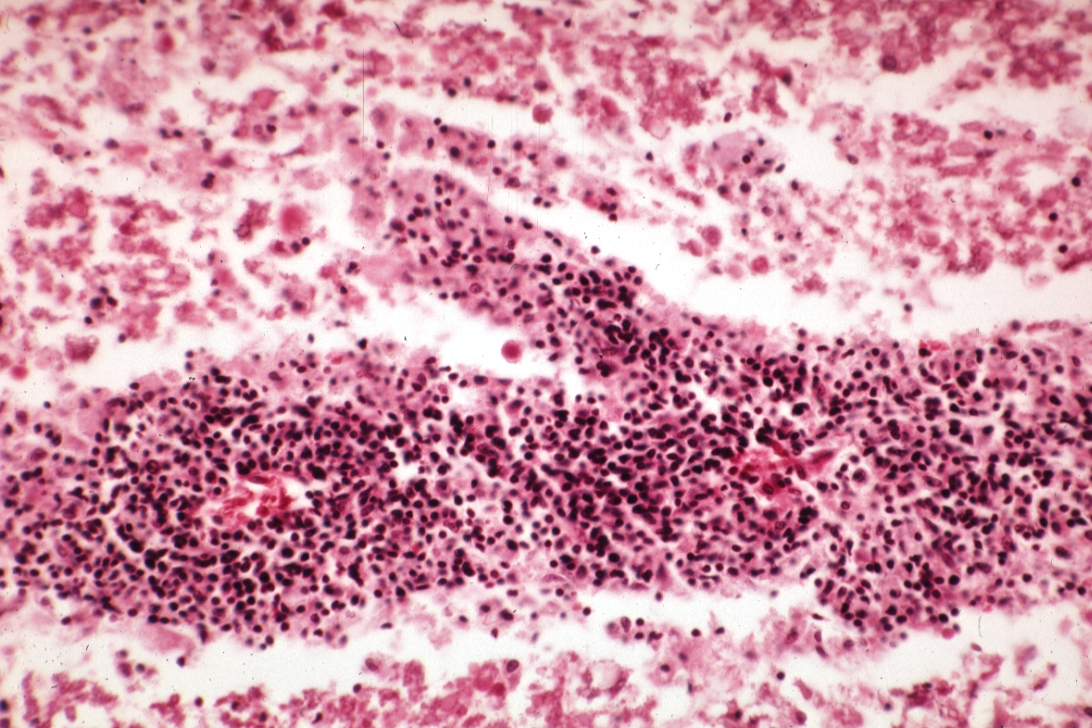

HISTOLOGY: NERVOUS: Brain: Lymphomatoid Granulomatosis: Micro med mag H&E upper cervical cord